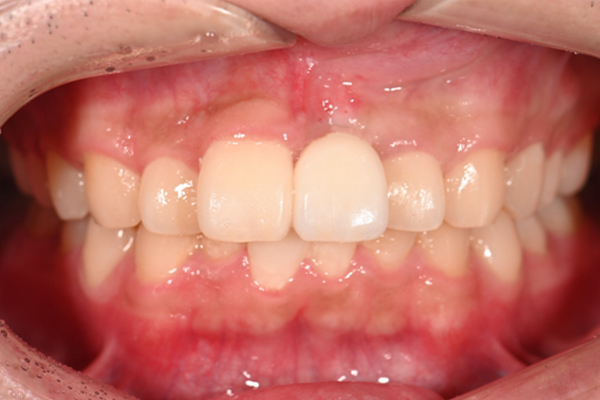

| 主訴 | 奥歯で噛めない、顎が痛い |

|---|---|

| 治療内容 | 奥歯のインプラント治療、前歯・奥歯の被せ物治療 |

| 治療期間 | 6ヶ月 |

| 治療費 | 350万円 |

| 治療リスク | 被せ物をつけた初期の段階で歯がしみることがある(時間とともに改善する) インプラント治療後に3日程度痛みと腫れを伴うことがある |